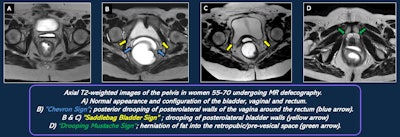

Signs of endopelvic fascial defects on MR defecography.

Individual components of the fascia are often not well visualized with a standard MRD technique, and defects are often inferred indirectly due to secondary findings. An endovaginal coil may improve visualization.